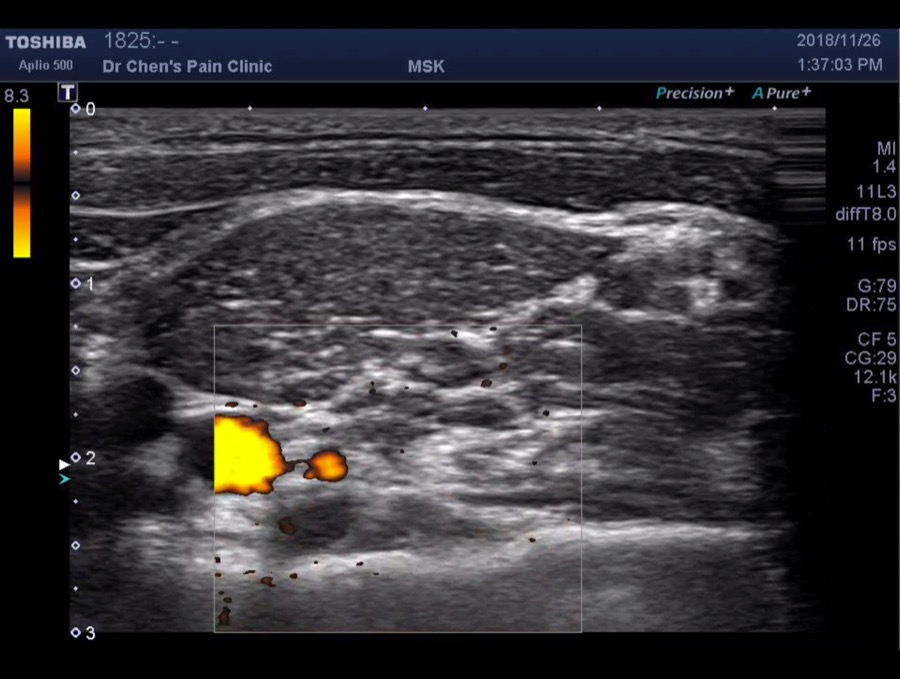

Radicula artery surrounding C8 nerve root

當操作頸椎注射時,一定要看清楚這條動脈,避免危險

Radicular artery below C8 nerve root